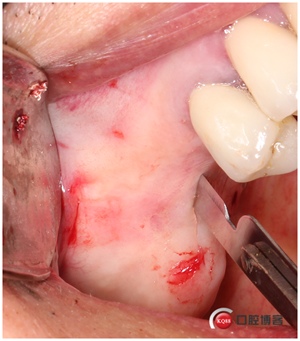

這時候我還沒有開窗,還沒有用器械剝離竇膜,但頰側(cè)骨壁和上頜竇膜已經(jīng)水壓撥開了。接下來我再開窗是不是就安全多了?看起來這種環(huán)切鉆挺嚇人的,那么鋒利的鋸齒。不要擔(dān)心了,這么多病例了,沒有一例在開窗時會撕裂膜的。當(dāng)然技巧還是有的,記得要反轉(zhuǎn),轉(zhuǎn)速200-500轉(zhuǎn),放心,切割能力一樣強(qiáng)大,4-6秒就可以磨下去。

看起來是不是像個藝術(shù)品?哈哈,自娛自樂一下,別見笑。

取下骨片,這才叫開窗了。